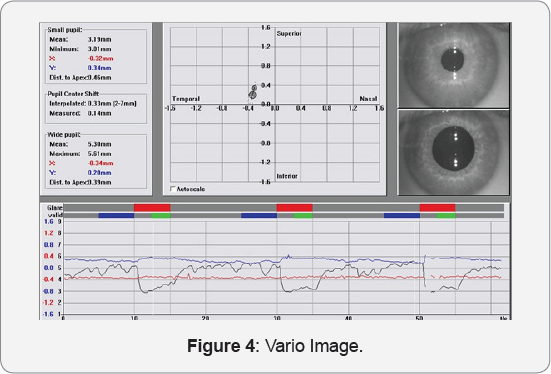

The clinical relevance for the clinician is that since corneal topography with this placido-based device is a cornerstone of evaluation, treatment, and postoperative management of laser cornea refractive surgery patients, these data can be extrapolated by the clinician to also give accurate pupillometry measurements and therefore potentially help with the surgical planning and/or postoperative assessment of potential visual complaints of the patients. (Figure 4)